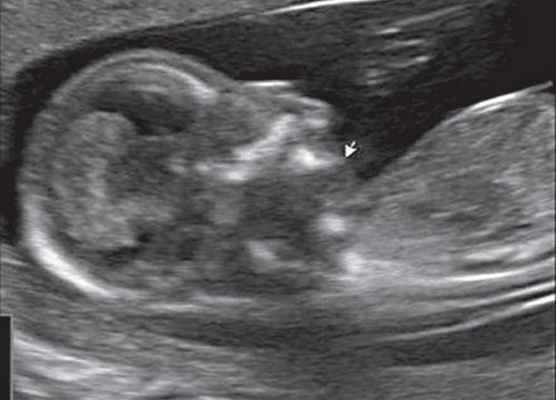

Рис. 1. Профиль плода с синдромом агнатии-голопрозэнцефалии в 12 нед беременности.

Рис. 2. Фенотип лица плода при синдроме агнатииголопрозэнцефалии в 12 нед беременности.